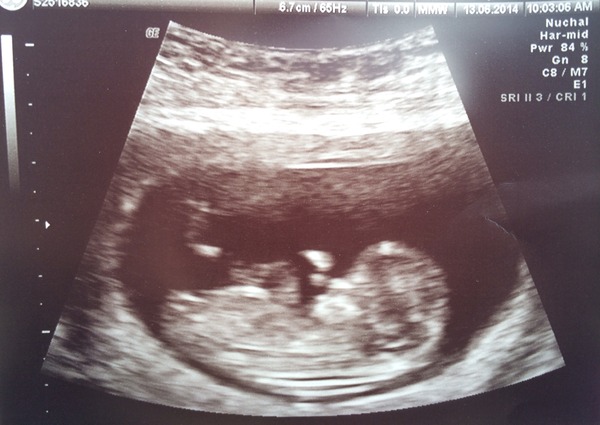

Tilly28 · 20/06/2014 18:33

And here's the piccy :-)

Loving the scan pics! Ok I'll join in too, here's baby Jesus (as DH is insisting on calling it!) the white floating thing is it waving!!

Didn't include the pic (slaps own forehead) here is baby Jesus...